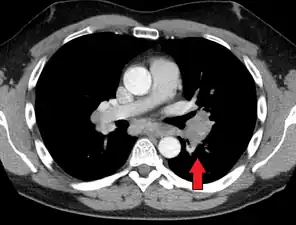

Hilar adenopathy especially on the person's left (AP CXR)

Hilar adenopathy especially on the person's left (lateral CXR)

Hilar adenopathy especially on the person's left (coronal CT)

Hilar adenopathy especially on the person's left (transverse CT)